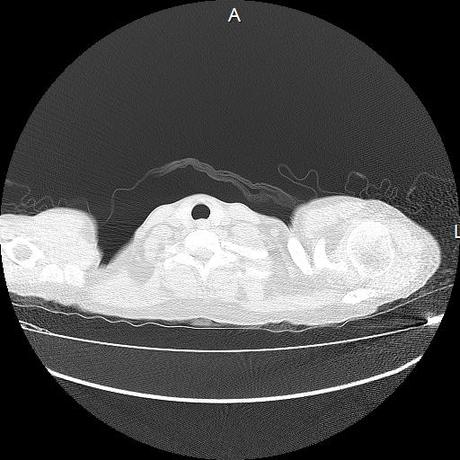

Se realiza volumen de tórax en fase simple, desde los opérculos torácicos hasta los hemidiafragmas, observándose:

Estructuras óseas sin evidencia de lesiones líticas, blásticas ni trazos de fractura. A nivel de cuerpo vertebral de T10 se observa nódulo de Schmorl que distorsiona el borde superior del cuerpo vertebral.

El parénquima pulmonar con areas parcheadas difusas en vidrio despulido combinadas con otras areas hipodensas de baja atenuación debidas a atrapamiento aéreo y engrosamiento intersticial y zonas de fibrosis de predominio en lóbulos medios e inferiores de ambos pulmones.

- LOS HALLAZGOS PUEDEN ESTAR EN RELACIÓN A NEUMOPATIA INTERSTICIAL PROBABLE ETIOLOGIA HIPERSENSITIVA VS AUTOINMUNE/BACTERIANA/FUNGICA.